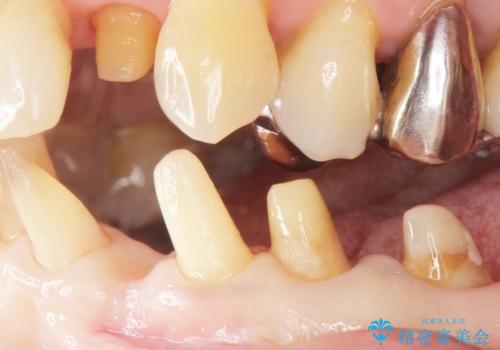

精査したところ、前歯の咬み合わせが反対になっていること、下の奥歯(下顎両側67)が4本欠損していることから動揺が生じていました。

入れ歯も抵抗があるとのことから、相談を重ね、今の状態では保存不可能な下の前歯(左下2)を抜去し、ブリッジや連結補綴により動揺を抑えることにしました。

また、咬み合わせが反対になっている上の前歯(左上2)も補綴で形を変えることにより、咬合を改善しました。

下顎大臼歯が欠損したままで今ある歯に負担がかかりやすいことから、長期的予後は保証できないことをご理解頂いた上で治療を行いました。